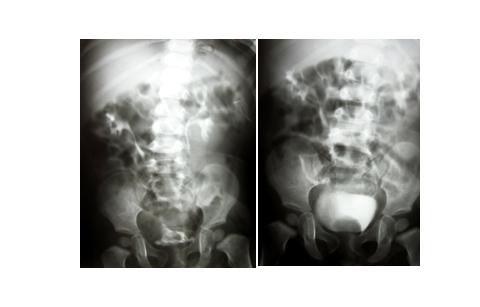

11-miesięczna dziewczynka z objawami nawracających zakażeń układu moczowego z powtarzającą się co kilka tygodni gorączką.

W wykonanym w rejonowym szpitalu USG stwierdzono obecność znacznie poszerzonego moczowodu po stronie prawej. Dziecko skierowano do Oddziału Urologii Dziecięcej, gdzie poszerzono diagnostykę obrazową. W badaniu USG stwierdzono znaczne poszerzenie górnego układu zbiorczego prawej nerki i znacznie poszerzony i wydłużony moczowód z hipoechogenną strukturą w pęcherzu. Wykonano badanie urograficzne, na podstawie którego rozpoznano: